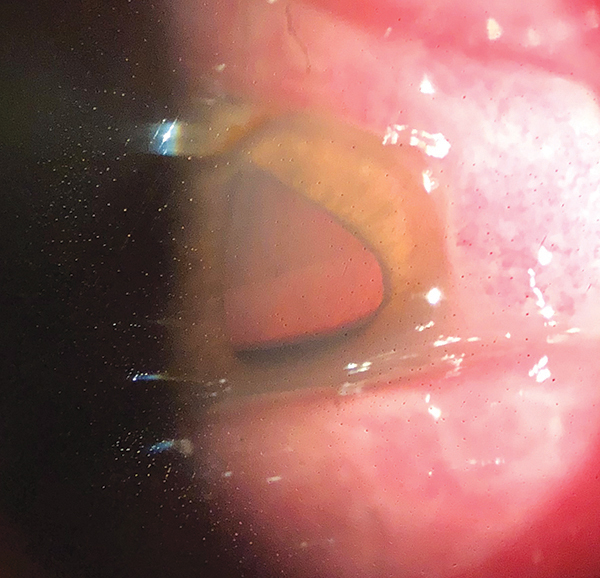

A la evaluación el paciente presentaba en ambos ojos una visión de movimiento de manos y a la biomicroscopía de ambos ojos se evidenciaba una hiperemia conjuntival, quemosis y una abundante secreción purulenta. En el ojo derecho, tras varios lavados de las secreciones, se pudo evidenciar una perforación corneal en hora 12, un prolapso de tejido uveal, discoria e hipotalamia (imagen 2). El ojo izquierdo presentaba adelgazamiento corneal periférico 360° (imagen 3).

Imagen 2